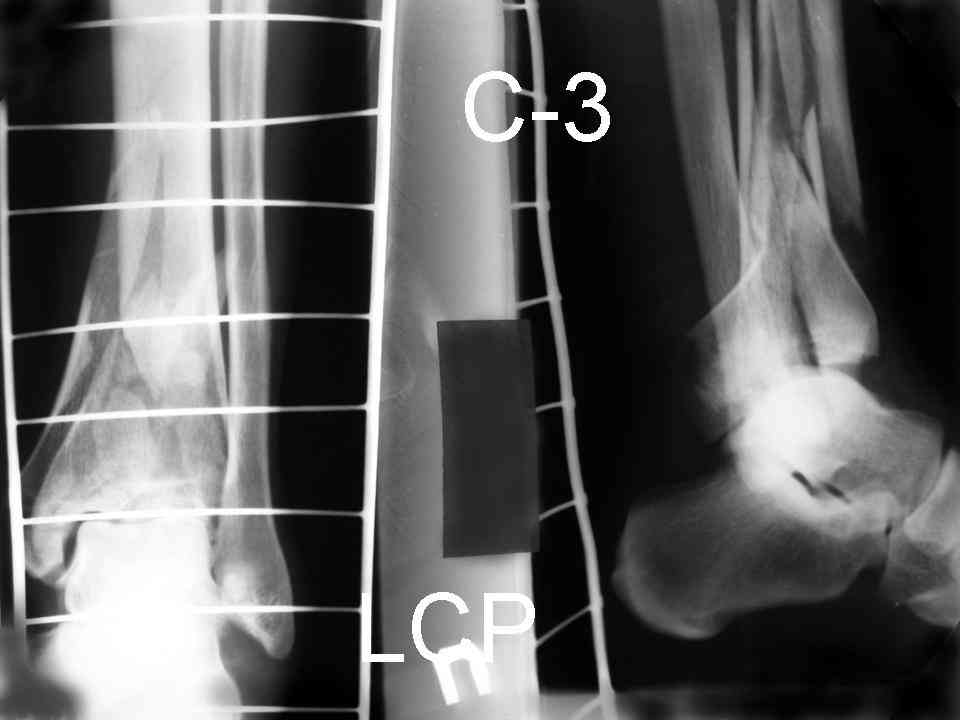

На рентгенограммах типичный перелом пилона по типу С-3. есть опыт до 100 открытых опреаций у нас в клинике. 20 примерно в год. Принцип один -все внутрисуставные переломы нуждаются в открытой репозиции и внутренней стабильной фиксации. При поступлении КТ не надо, так как получается только нагромождение костей. Истинной картины нет. Главное восстановить длину малоберцовой кости - это ключ к успеху. При поступлении меньше всего надо думать о сосудистых расстройствах, т.к. сама операция и репозиция даже сначала частичная даёт улучшение сосудитых нарушений. Причём очень быстро. Операция в 2этапа. При поступлении доступ позади наружной лодыжки, причём обязательно. После этого репозиция малоберцовой кости и фиксация пластиной 1/3 трубки под винт 3,5. Дренаж и любой аппарат наружной фиксации. Затем после спадения отёка на 5-7-10 день аппрат снимается и дугообразный разрез спереди от медиальной лодыжки 10-12 см. Главной чтобы расстояние между 1 и вторым разрезом было не меньше 7-8 см. Тогда не будет некрозов лоскутов. Таранная кость используется как матрица на неё укладываются отломки и фиксируются пицами. Ренг-контроль. Отломки лежат все отдельно, но ничего не высыпется. При переломах С-3 всегда нужна костная пластика (из крыла). Фиксация пластиной лист клевера простой или LCP. Гипс не нужен. Дренаж до 48 часов. Операция длится 3-4 часа обязательно без жгута. Посылаю примерно такой же случай.

Послала ещё два снимка, если не пройдут, пошлю ещё. Дрягин. Если есть вопросы, готов ответить.